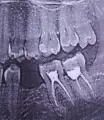

Вам необходимо обратиться к врачу стоматологу-терапевту, сделать рентгеновский снимок. Врач оценит состояние тканей, окружающих зуб, а также состояние тканей самого зуба.